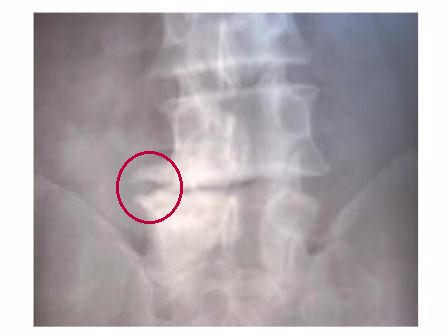

Osteofiti

Nel referto è spesso indicata la presenza di "becchi osteofitici".

Indicano la presenza di osso in eccedenza, indice di ripetuti conflitti di inadeguatezza e svalutazione di una certa gravità a carico dell'osso.

Il tentativo della Natura di irrigidire una articolazione che viene percepita incapace di adempiere alla propria funzione.